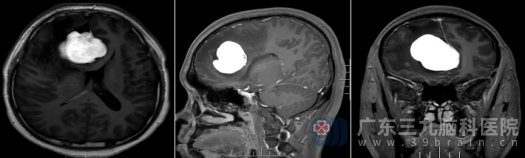

入院后,更精密的术前头颅MR检查显示:在患者右侧额部大脑镰旁,一个大小约47×40×44mm的肿瘤清晰可见,体积堪比一个鸽子蛋。

“肿瘤的位置非常关键,”主管医生解释道,“它正好压迫到与视觉信息穿入相关的右侧视神经,这是导致右眼中心视力模糊的直接原因。”

神经外十科团队组织了多学科讨论。从影像特征看,虽然首先考虑常见的脑膜瘤,但也需要警惕孤立性纤维性肿瘤等其他可能。无论病理类型如何,这个位置的肿瘤都如同“不定时炸弹”,必须尽快手术。